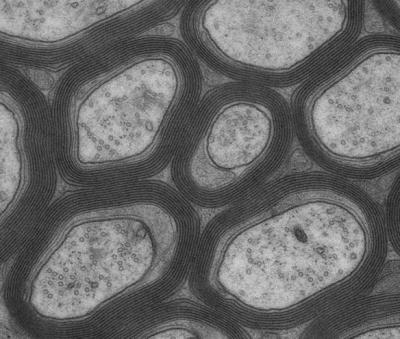

Oligodendrocytes are a group of highly specialised glial cells in the central nervous system. They are responsible for the formation of the fat-rich myelin sheath that surrounds the nerve fibres as an insulating layer. The comparison with the coating on electricity cables is an obvious one; however, myelin can do much more than act as the insulating layer on electricity cables: it increases the transmission speed of the axons and also reduces ongoing energy consumption. The extreme importance of myelin for a functioning nervous system is shown by the diseases that arise from a defective insulating layer, such as multiple sclerosis.

And this is precisely what the scientists observed in their mice: the animals' myelin was initially formed in the normal way. The loss of the mitochondrial respiratory chain, which started at this point, did not appear to affect the glial cells in the central nervous system. Even one year later, there were no neurodegenerative changes in the brain to be observed. The scientists assume that in the early weeks of life – a phase characterised by maximum energy requirement – the mutated oligodendrocytes still rely on many intact mitochondria. All of the more mature oligodendrocytes later appear to reduce the mitochondrial respiration and set it to energy generation through increased glycolysis. This has the advantage in healthy glial cells that the metabolic products which arise during the breaking down of glucose can be used as components for myelin synthesis. In addition, the lactic acid that arises in the oligodendrocytes can be given to the axons where it can be used to produce energy with the help of the axon's own mitochondria.

"The complete loss of the respiratory chain in the deliberately modified oligodendrocytes probably elevates a developmental step that unfolds naturally," explains Nave. Thus the loss of glial mitochondria does not result in the deterioration of the energy supply to the axons but, conversely, to an oversupply of exploitable lactic acid. The affected nerve pathways themselves have no problem demonstrably in metabolising the lactic acid from oligodendrocytes. Transport proteins ensure the rapid transfer of the lactic acid between the oligodendrocytes and their myelinated axons.